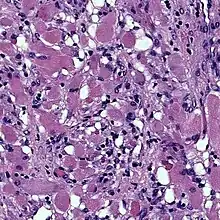

Cardiac rhabdomyomas are the most common primary tumor of the heart in infants and children. It has an association with tuberous sclerosis.[2] In those with tuberous sclerosis, the tumor may regress and disappear completely, or remain consistent in size. A common histological feature is the presence of Spider Cells, which are cardiac myocytes with enlarged glycogen vacuoles separated by eosinophilic strands, resembling the legs of a spider.